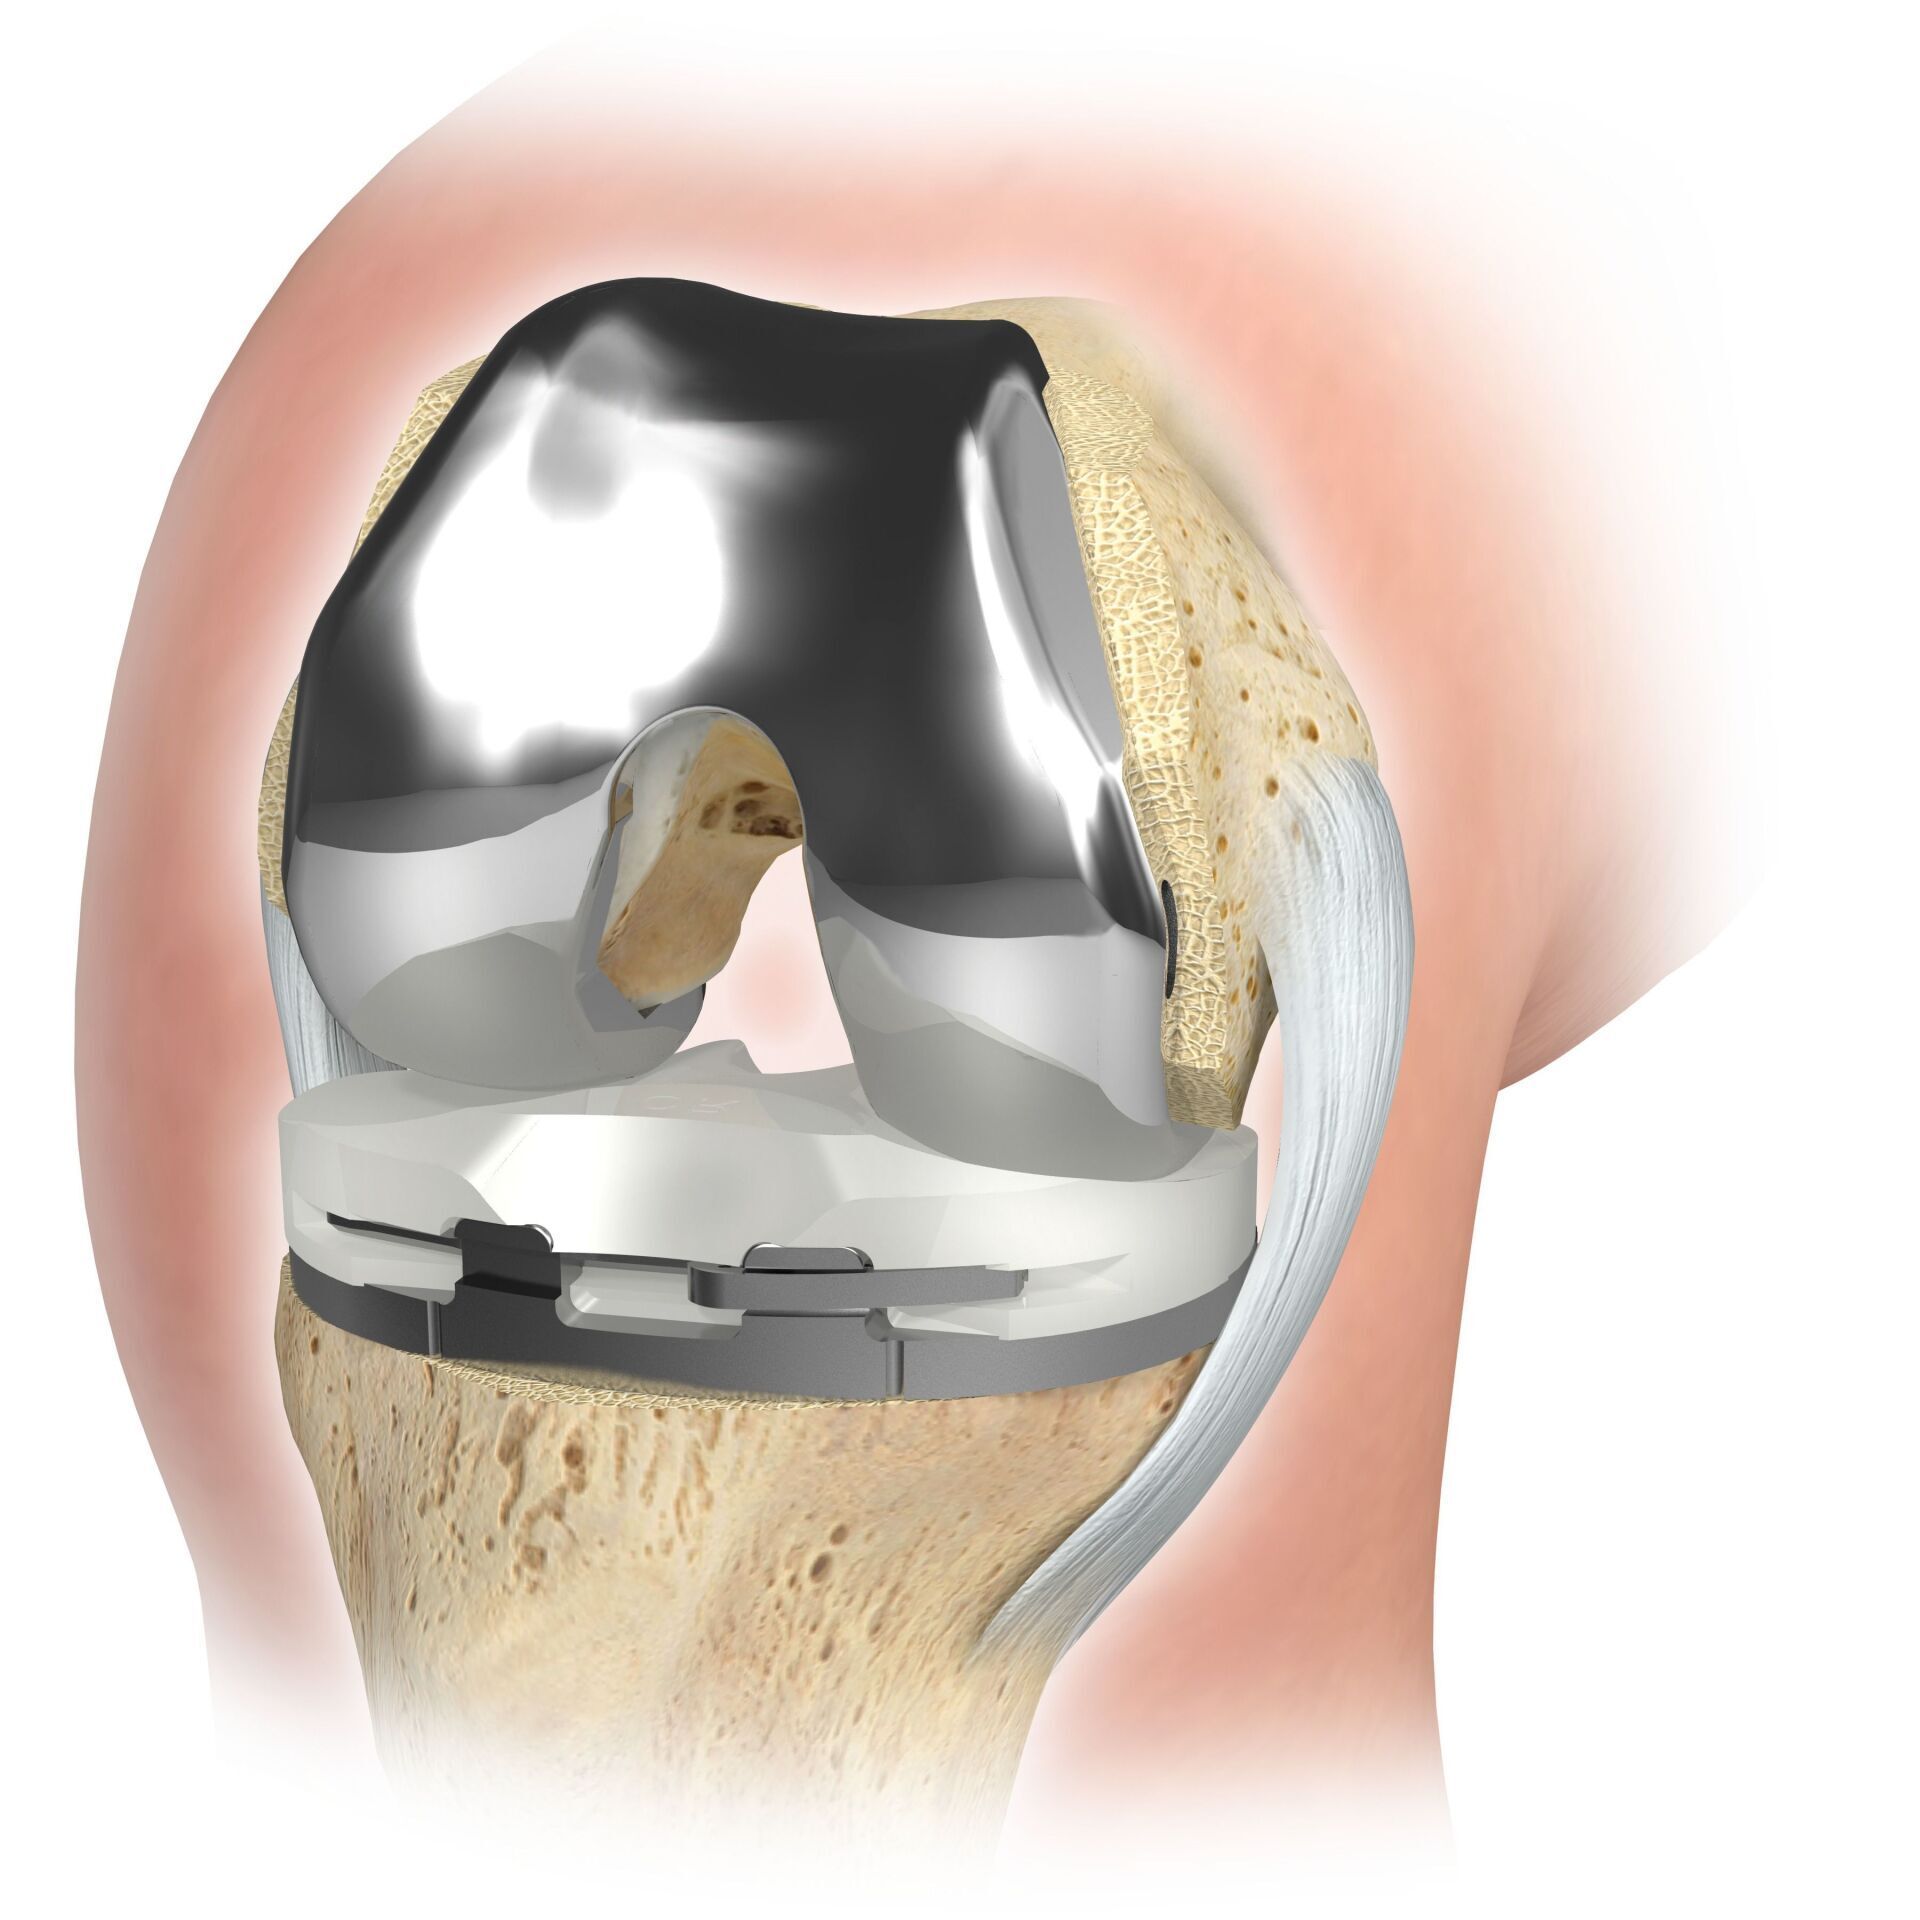

Surgical skills: Specialists in knee arthroplasty are highly qualified surgeons who perform the actual surgery. They are proficient in various surgical techniques, including total knee arthroplasty and partial joint replacement (eg sled prosthesis), and select the most appropriate option.

Intraoperative expertise: During the procedure, the knee replacement specialist removes the damaged bone and cartilage and replaces it with an artificial joint made of materials such as metal and plastic, ensuring the correct alignment and fit of the components to restore normal function to the knee.